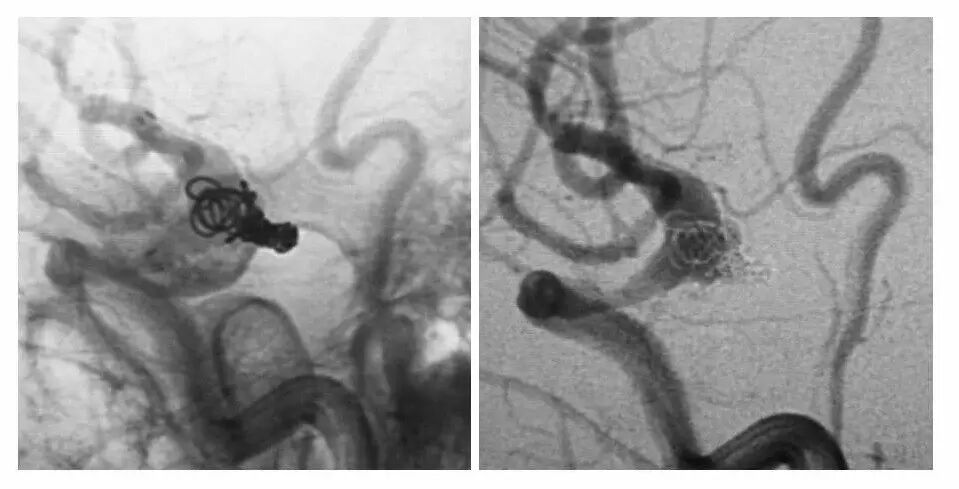

今天为大家分享的是“强生医疗CNV-神经介入专栏”第十五期,由首都医科大学宣武医院何川教授带来的“颅内动脉瘤介入治疗”精彩讲课视频及PPT,欢迎观看、阅读。文章仅代表作者个人观点,如有不同见解,欢迎同道斧正!